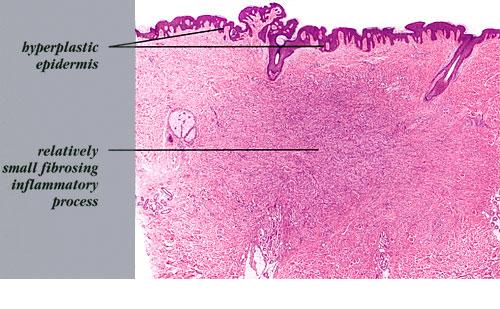

The overlying epidermis is usually acanthotic. Pseudoepitheliomatous hyperplasia and a basaloid proliferation may be noted. The hyperplasia may be caused by the action of fibroblasts on epidermal keratinocytes.23  Basal cell carcinomas occurring upon a dermatofibroma have been reported. Increased pigment may be seen, which may be iron or melanin. Most lesions display a grenz zone of normal papillary dermis overlying the tumor.

The bulk of the tumor is within the mid dermis where no capsule is present and the periphery of the lesion blends with the surrounding tissue. Whorling fascicles of a spindle cell proliferation with excessive collagen deposition are characteristic. At the periphery, the spindle cells characteristically wrap around normal collagen bundles (see the images below). Occasionally, melanocytes have been reported to be interspersed amongst the spindle cells.24